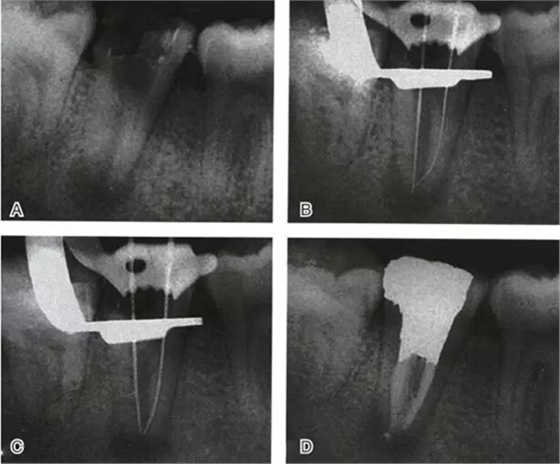

圖6 Ⅱ型C形根管治療典型病例,A:初尖銼片,B:主尖銼片,C:根充片,D:術后片

圖7 Ⅲ型C形根管治療典型病例,A:初始片,B:初尖銼片,C:主尖銼片,D:充填片